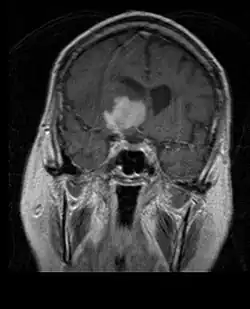

L'IRM montre généralement une lésion de contraste massive impliquant le cervelet. Comme mentionné ci-dessus, le médulloblastome a une forte propension à infiltrer localement les leptoméninges ainsi qu'à se propager à travers l'espace sous-arachnoïdien, impliquant les ventricules, la convexité cérébrale et les surfaces leptoméningées de la colonne vertébrale. Par conséquent, il est nécessaire de mettre en résonance tout l'axe crânio-spinal.

Les méningiomes sont les tumeurs cérébrales extrinsèques ou extra-axiales intracrâniennes les plus courantes qui proviennent des cellules de l'arachnoïde, la membrane qui recouvre le cerveau et la moelle épinière. L'incidence de cette néoplasie est d'environ 2 cas par an pour 100 000 habitants. Ils sont plus fréquents chez les femmes dans leurs sixième et septième décennies. Leur fréquence est plus élevée chez les patients atteints de neurofibromatose de type 2. La perte du chromosome 22 est caractéristique des méningiomes, bien que la signification pronostique de cette découverte soit encore incertaine.

Les patients atteints de méningiome peuvent présenter des symptômes typiques d'une lésion crânienne massive, notamment des convulsions et des déficits neurologiques focaux. détecté sur la tomodensitométrie et l'imagerie par résonance magnétique pour d'autres raisons. Cette tumeur de résonance a un aspect caractéristique, consistant généralement en un rehaussement de contraste uniforme le long de la dure-mère avec une séparation nette du parenchyme cérébral. Une autre caractéristique, bien que non présente dans tous les cas, est la soi-disant "queue durale", représentée par un renflement qui s'étend au-delà de la lésion et indique le point d'ancrage dans la dure-mère.